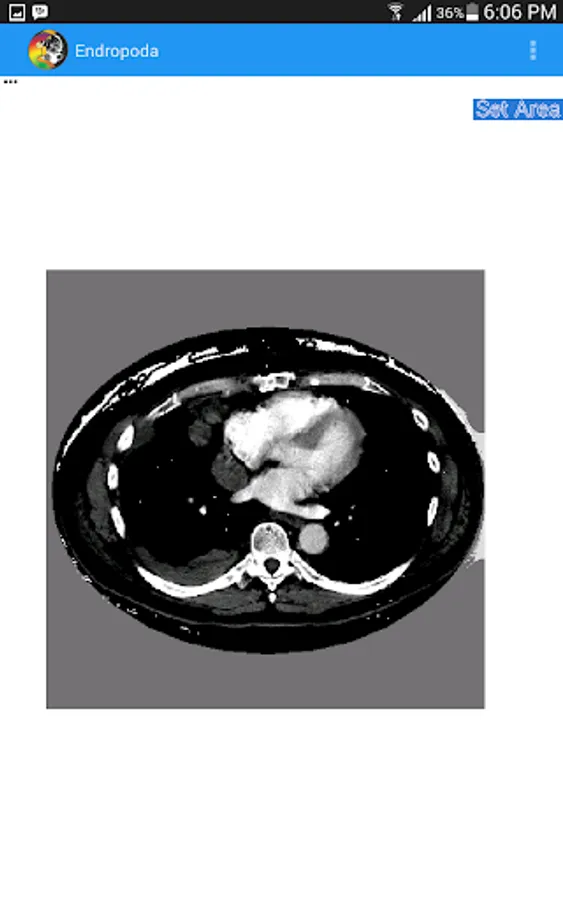

- Planning : In planning mode, user can create a region of interest on CT-Scan image to eliminate the background area and also can create cancer area that will be treated with radiation